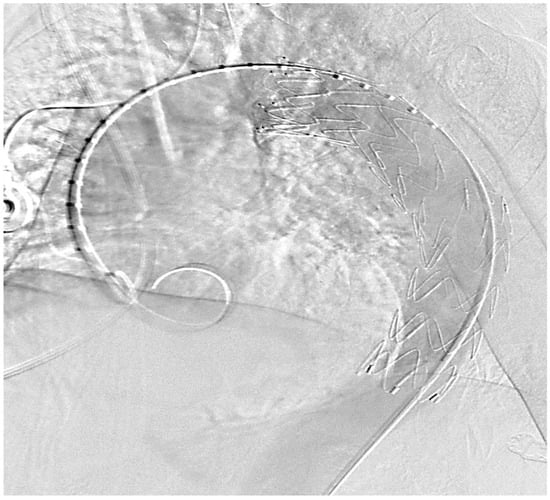

4.2. Aortic Stent Implantation